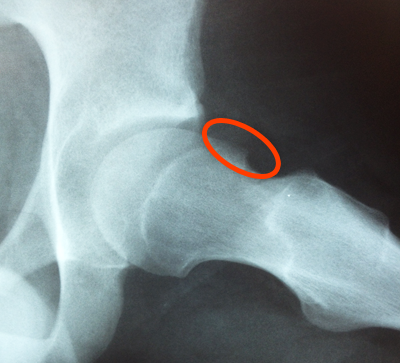

Sometimes loose bodies – typically from cartilage or bone – can cause instability of the hip joint. This can lead to a sudden, sharp pain in the hip, sometimes causing a fall.